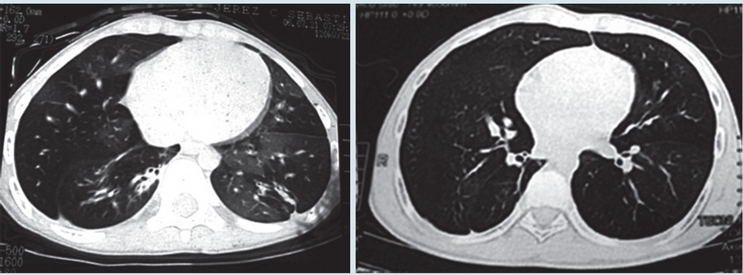

En las Figuras 1 y 2 se observan imágenes diagnósticas de algunos de nuestros pacientes y en la Figura 3 la evolución favorable de la tomografía (en un caso) después de varios años de seguimiento. En nueve casos se realizó exploración funcional respiratoria encontrando obstrucción significativa de la vía aérea en seis, obstrucción leve en dos y ausencia de obstrucción en uno; en 3/8 pacientes se observó reversibilidad del volumen espiratorio forzado en el primer segundo (VEF1). Se hizo seguimiento de la función pulmonar en cuatro pacientes observándose deterioro de la misma en tres (Figura 4). En cuanto a la presión pulmonar se encontró inicialmente elevada en el 43% de los casos, observándose en su seguimiento, disminución en cinco y aumento en uno.

Con relación a las imágenes diagnósticas, todos los pacientes tenían patrón de mosaico en la tomografía de tórax, pues era un criterio de inclusión. Encontramos bronquiectasias en el 33% de los casos, hallazgo frecuente en la bronquiolitis obliterante post-infecciosa reportándose en el 60% de los casos en Fortaleza (Brasil),2 en el 36% en el País Vasco (España) 10 y en el 32% en Porto Alegre (Brasil).4 La identificación de las bronquiectasias es importante pues implica la implementación de medidas terapéuticas como la administración de antibióticos y la realización de terapia respiratoria.

En los casos en que se hizo tomografía de control, con un rango de tiempo entre los dos estudios de 31 a 80 meses, observamos mejoría en las imágenes en 6/8 pacientes. No encontramos en la literatura datos sobre seguimiento de imágenes en bronquiolitis obliterante post-infecciosa que nos permitan hacer una comparación al respecto.